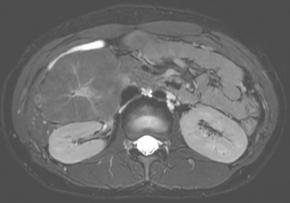

• T2 fat suppressed image

Comments This case report describes a hepatic tumor that was incidentally discovered in a pediatric patient with no underlying liver disease. On color Doppler imaging, there were findings suggestive of a central stellate scar, and the corresponding area demonstrated high signal intensity on T2-weighted MRI. Furthermore, on contrast-enhanced MRI, the lesion, excluding the central scar, showed homogeneous enhancement during the arterial phase and persistent enhancement in the portal venous phase with no evidence of washout. An additional finding, though not presented in the primary text, was homogeneous high signal intensity in the hepatobiliary phase (sparing the central scar). All of these findings are characteristic of focal nodular hyperplasia.